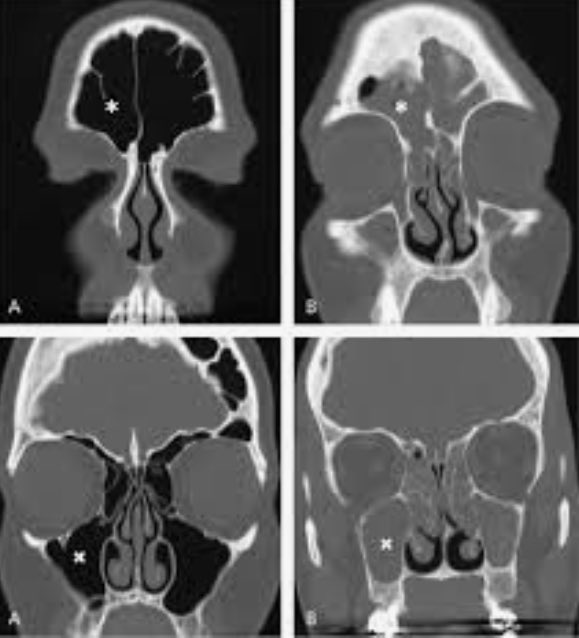

يجب ان تكون الاعراض ناتجة عن حساسية انف وذلك باختبار الوخز الجلدي للمكونات الحساسية( حبوب اللقاح وغيرها) ونسب #ارتفاع_الغلوبين IgE وخلايا الحمضات #eosinophils

يجب ان تكون الاعراض ناتجة عن حساسية انف وذلك باختبار الوخز الجلدي للمكونات الحساسية( حبوب اللقاح وغيرها) ونسب #ارتفاع_الغلوبين IgE وخلايا الحمضات #eosinophils

نحتاج الى 3 من ٥ مما ذكرا سابقا بالاضافة الى التدخل الجراحي السابق لكى يكون العلاج مناسبا وحسب ما توصى به المراجع الطبية